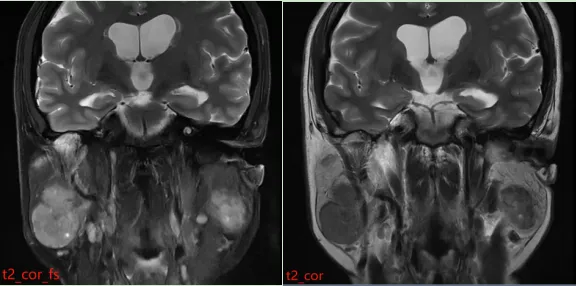

患者接受了磁共振(MR)检查,影像表现如下:

MR 表现:双侧腮腺浅叶下极见结节状略混杂信号,T1 以低信号为主、T2 以 稍高信号为主,DWI 呈稍高信号,ADC 图呈稍低信号,边界清晰,增强扫描病变中等强化,强化较均匀,其内见点状无强化影。